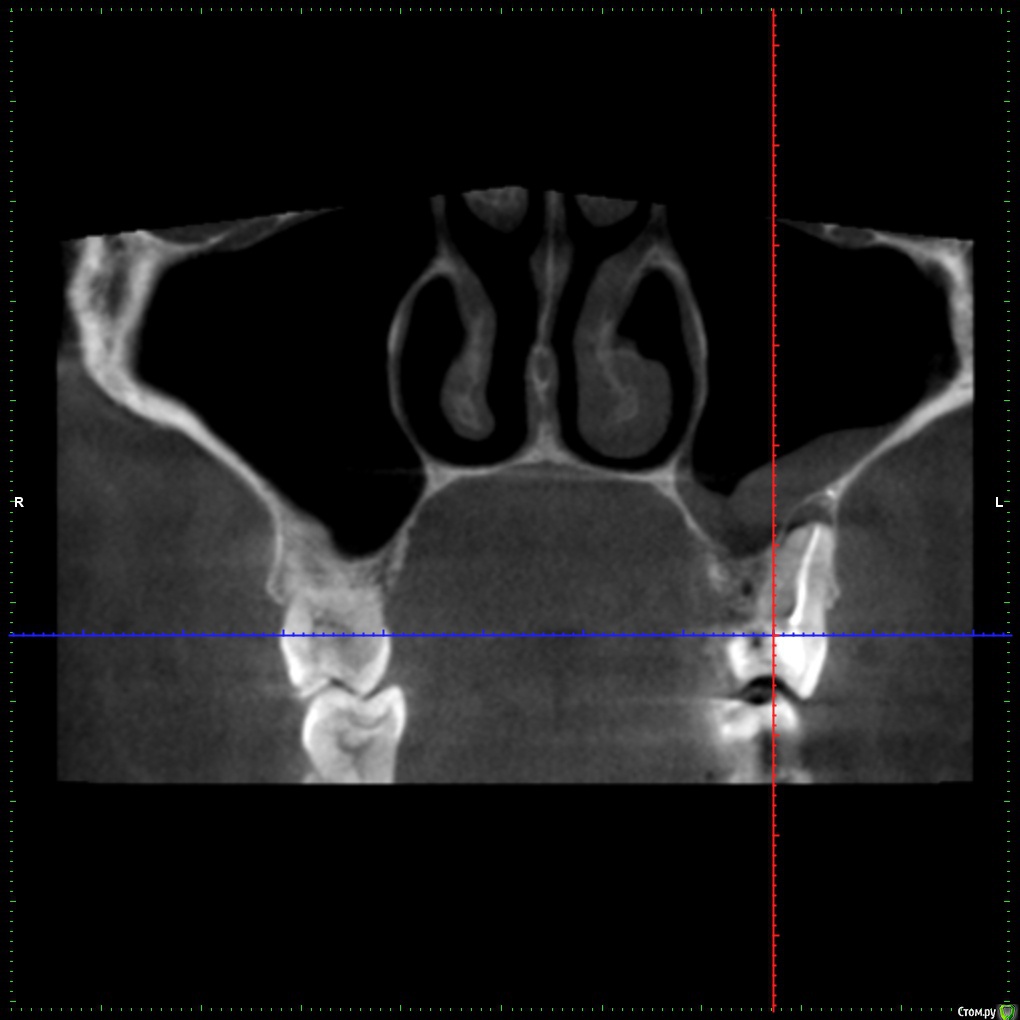

Freemind Опубликовано 13 июня, 2020 Поделиться Опубликовано 13 июня, 2020 Здравствуйте, уважаемые добрые врачи!Мне 32, мужеского полу. В начале мая обратился к своему стоматологу с жалобой на боль на холодное/горячее, точнее зуб реагировал на воду даже комнатной температуры (20-22 градуса), при надкусывании не болел. Мне казалось что это 5-й сверху слева. Он был два года назад лечен от пульпита, но сразу после лечения была странная симптоматика (хотя и пил ибупрофен 10 дней по рекомендации стоматолога): зуб не болел, не реагировал на холодное/горячее, но я его как-бы чувствовал при надкусывании/постукивании. Особого дискомфорта это не доставляло, поэтому забил и так и ходил. На приеме внешних признаков проблем не обнаружилось, сделали визиографию, увидели кисту, вскрыли зуб, три приема в течении 3- недель какие-то лечебные пасты(?) накладывали. Лучше становилось временами.Далее направил он меня на КТ. На снимках: киста оказалось над шестым, корни почти до пазух, гайморит (отчетливое воспаление, хотя из симтомов только периодические слабые головные боли в области левого виска и скудные желтовато-зеленые выделения по утрам из носа при сморкании). Этот шестой был лечен от пульпита лет 6-7 назад у другого стоматолога. Вскрыл его, обнаружил один не леченый канал (Сам я этого не вижу на КТ). Лекарство. К второму приему по 6-му зубу вроде стало получше,- на воду комнатной температуры точно перестало болеть, на откровенно холодное чаще реагирует, чем нет. Направил он меня к ЛОРу, который прописал пока назонекс, предложил варианты: 1) либо лечить зуб, смотреть динамику и далее толи 1.1.делать операцию на пазухе, толи 1.2. удалять зуб, опять смотреть. 2) сразу удалять, смотреть динамику. На сейчас: уже три раза лечебная паста(?) на 6-й. Периодически головные боли несильные, периодически реагирует на холодное и чуть поднывает. А бывает день вообще не замечаю никакого дискомфорта. Вопросы:1. На снимке киста?, есть ли перфорация? - мне кажется по снимку видно, что при лечении одного из корней (6-7 лет назад) пробита пазуха - может гайморит от перфорации, а не от кисты?.2. Почему мне субъективно кажется, что болевые ощущения когда они есть идут от 5-го, хотя киста над 6-м? Даже когда нет никаких болей, 5-й все проявляет эту странность - "как бы чувствую" его в корню (при постукивании ощущение очень отдаленно сродни щекотки).3. Стоит ли уже залечивать на постоянную эти зубы? или удалять 6-й? или сделать снова КТ сейчас? Может эта киста вообще рассосаться? Еще одно уточнение, не уверен, что относится к теме. В конце февраля было 2 дня дико плохое самочувствие - сначала только сильная ломота во всем теле, затем прибавилась температура 38. Еще пару тройку раз такое повторялось в слабой форме без температуры до середины мая. Т.е. это точно не ОРВИ была. Обследоваться начал - флюорография чистая., анализы на ВИЧ, гепатиты не успел - больницы на карантин закрылись (хотя образ жизни сильно далек от факторов риска этих инфекций). В любом случае исчезновение этих приступов ломоты совпало с началом лечения зубов - хз совпадение нет ли? С уважением, Александр. Извините за такой опус, просто что-то боязно становиться за свою тушку. P/S: вся КТ здесь https://drive.google.com/file/d/1gya4SSUk5vu8DrihvHP74CF-IKWj9XCk/view?usp=sharing. Ссылка на комментарий

St. Опубликовано 14 июня, 2020 Поделиться Опубликовано 14 июня, 2020 Добрый день. 1. На снимке киста? На снимке периодонтит, по простонародному "киста". И плюс реакция слизистой оболочки гайморовой пазухи на него. есть ли перфорация? Перфорация чего? в зубе - не видно мне кажется по снимку видно, что при лечении одного из корней (6-7 лет назад) пробита пазуха - может гайморит от перфорации, а не от кисты?. Есть немного выведенного материала, это не критично. 2. Почему мне субъективно кажется, что болевые ощущения когда они есть идут от 5-го, хотя киста над 6-м? Покажите срезы в области 5 3. Стоит ли уже залечивать на постоянную эти зубы? Имеет смысл попробовать и посмотреть на динамику. через 6 мес сделать контрольные снимки. сделать снова КТ сейчас? Раньше 6 мес после постоянной пломбировки каналов не имеет смысла Может эта киста вообще рассосаться? Да 2 Ссылка на комментарий

Freemind Опубликовано 16 июня, 2020 Автор Поделиться Опубликовано 16 июня, 2020 Огромное Вам спасибо! Покажите срезы в области 5 Ссылка на комментарий

St. Опубликовано 16 июня, 2020 Поделиться Опубликовано 16 июня, 2020 Я бы начинала перелечивание с 6, если дискомфорт пройдет, то ок. Если нет, то перелечивать и 5 ( по кт канал заполнен на всю длину вполне плотно, но кость за пределами корня неоднозначная..) Ссылка на комментарий